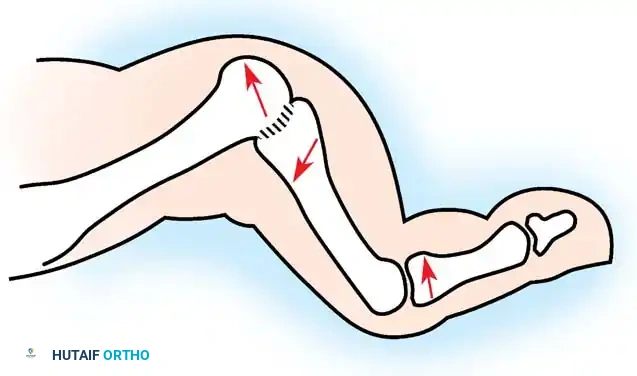

Fig. 81-7 Biomechanical progression. (A) Normal alignment and balance of the MTP joints and extensor sling. (B) Progressive dorsal subluxation and lesser toe deformity. (C) End-stage deformity with complete MTP dislocation; the proximal phalanx is ankylosed to the dorsal aspect of the metatarsal head, and the plantar fat pad has migrated distally.

Gradually, this concentrated extension force completely dislocates the MTP joints. At end-stage disease, the proximal phalanx rests entirely on the dorsal aspect of the metatarsal neck.

- Intrinsic Muscle Dysfunction: As the MTP joints subluxate dorsally, the intrinsic muscles (lumbricals and interossei) shift dorsal to the flexion-extension axis of the MTP joints. Consequently, they lose their primary ability to flex the MTP joint. Furthermore, their secondary function—extending the proximal interphalangeal (PIP) and distal interphalangeal (DIP) joints—is severely weakened.

- Extrinsic Overpowering (Tenodesis Effect): With the intrinsics mechanically disadvantaged, the extrinsic long toe flexors (flexor hallucis longus and flexor digitorum longus) exert an unopposed pull, drawing the PIP and DIP joints into rigid flexion.

- Extensor Mechanism Concentration: The inability of the extensor digitorum brevis (EDB) and extensor digitorum longus (EDL) to extend the middle and distal joints compounds the deformity. Because of reduced tendon excursion secondary to MTP joint hyperextension, all the extension moment of the extensor hallucis longus (EHL), extensor hallucis brevis (EHB), EDL, and EDB is concentrated entirely at the MTP joints.